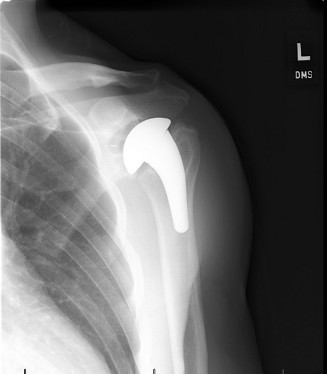

A sophomore, high school wide receiver presents to your clinic at the beginning of his football season. He reports a dislocation event after being tackled; his shoulder was “put back in place” by the on-field athletic trainer. A CT scan taken in the hospital today is shown (Fig. 2–33). He has been recruited by numerous colleges, plans to play at a division 1 school, and is very eager to return to the field.

Figure 2–33

The correct answer is (E). A large bony fragment (>20%) makes the failure rate with nonoperative treatment (Answers A, B) unacceptably high. This question is meant to illustrate the challenges associated with treating an in-season athlete and highlighting the indications for surgery after a first time dislocation event. Typically, early in a season, providers will initiate an aggressive PT program and try and return athletes to the field within a few weeks so that they can play out the remainder of the season. Towards the end of the season, when there is insufficient time to rehab a patient, one may choose early surgery so that the patient has maximal time to recover prior to the next season. In this case, even though the

patient is extremely motivated to return to the field and has only sustained a single dislocation event, the large bony Bankart lesion behooves surgical treatment. The best option for him would be to have early surgery and have a maximal amount of time to prepare for his senior season. A Latarjet procedure (Answer C) is used for patients with recurrent anterior instability and significant glenoid bone loss, and the Magnuson–Stack procedure (Answer D) is a largely historic procedure that was used for recurrent anterior instability. Objectives: Did you learn...? The common presentation of a patient with shoulder instability?